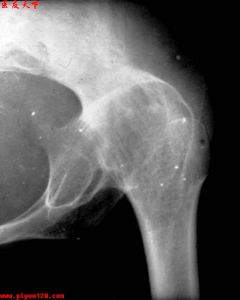

局限性骨膿腫--X片局限性骨膿腫通常發生於長骨的乾骺端,多見於脛骨、股骨與肱骨。產生局限性膿腫的主要原因是在感染時由於細菌毒力低而機體的抵抗力相對強時感染可被局限於骨的乾骺端,形成局限性骨膿腫。本病因最早由英國醫生Brodie(1880)首先報導,故亦Brodie膿腫膿腫內為黃白色稠厚膿液或肉芽膿液培養可無細菌生長。膿腫中期為炎性肉芽組織所替代後期則形成感染性瘢痕組織。

本病多發於青少年,以脛骨下端及上端、橈骨下端等處多見,亦可見於股骨及肱骨。患者多有急性感染史,以後遺留有局限性疼痛。重者可有紅熱、腫脹等局部表現,但少有嚴重者。一般無全身症狀可有間歇期,並呈急性發作。

本疾病多發生於青壯年,多見於脛骨上端,股骨下端和上端、肱骨上端等長骨兩端。本病主要是由於感染引起,故注意平時的體育鍛鍊,增加身體的抵抗力,有利於本病的預防。